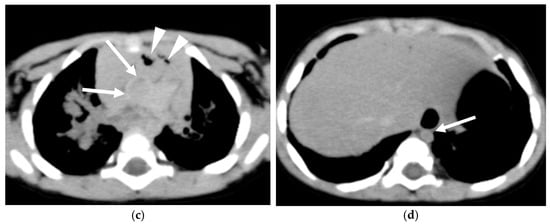

Supplementary Tables S1 and S2 present clinical information and CT findings of the non-ROSC (Figure 1) and ROSC groups (Figure 2), respectively. The non-ROSC group showed significantly higher incidences of several findings compared to the ROSC group, including brain swelling (84% vs. 12.5%; p < 0.001), loss of cerebral gray-white matter differentiation (74% vs. 37.5%; p = 0.033), symmetrical consolidation/ground-glass opacity (95% vs. 50%; p = 0.017), cardiomegaly (84% vs. 25%; p = 0.006), hyperdense aortic wall (84% vs. 0%; p < 0.001), narrowed aorta (100% vs. 0%; p < 0.001), gas in the mediastinum (80% vs. 0%; p < 0.001), and hepatomegaly (79% vs. 12.5%; p = 0.002). Neither pericardial effusion nor subcutaneous fatty edema was observed in any case. There were no significant differences between the non-ROSC and ROSC groups in the incidence of loss of cerebral gray-white matter differentiation, hyperdense intracranial venous sinus, symmetrical/asymmetrical consolidation/ground-glass lung opacity, cardiomegaly, hepatomegaly, dilated inferior vena cava, dilated gastrointestinal tract, or gas in the upper abdominal organs. A summary of the differences in the WBCT findings between the non-ROSC and ROSC groups is provided in Table 2.

Figure 2.

Four-month-old boy with ROSC (case No. 6 in Table S2). (a) No symmetrical or asymmetrical lung consolidation/ground-glass opacity of the lungs was observed. (b) In the mediastinum, mild cardiomegaly was noted, but no hyperdense aortic wall was identified. (c) A dilated gastrointestinal tract was observed.